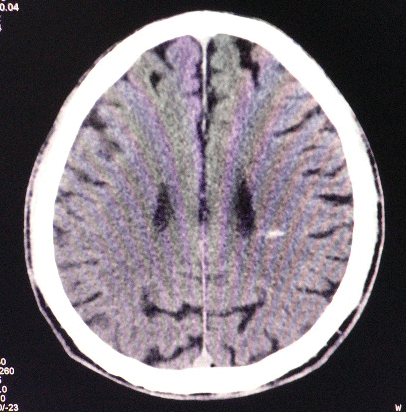

以下是引用狙击手在2007-4-8 22:45:00的发言:[br]出血?从患者的症状考虑病灶应该在左侧大脑半球的基底节区或颞顶部,如此小的病灶引起上述症状的可能性不大,患者可能有梗塞(时间短,目前ct还看不见)或是tia发作,再者像这样的线条形出血的确不多见,但还是有可能的,曾经碰到有外伤类似出血,复查后消失,所以还是慎重一点,短期复查即可。

以下是引用dyqct在2007-4-8 16:25:00的发言:[br]支持左侧放射冠区少量出血。